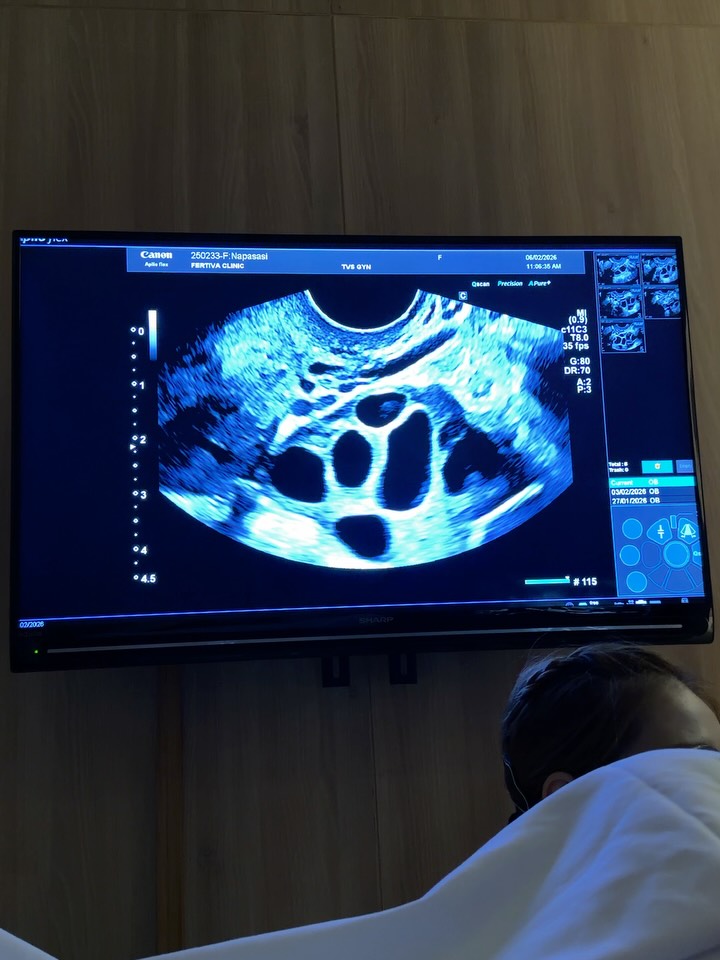

โดยสาวมายด์ได้โพสต์ภาพสุดประทับใจผ่านโซเชียลส่วนตัว ระบุว่าภารกิจฝากไข่เสร็จสมบูรณ์เรียบร้อยแล้ว ได้ไข่ทั้งหมด 19 ใบ ซึ่งเป็นไปตามเป้าหมายก่อนที่เธอจะมีอายุครบ 35 ปีบริบูรณ์ ยอมรับว่าช่วงแรกแอบลุ้นและตื่นเต้นทุกวันที่ต้องฉีดยากระตุ้น เพราะกลัวเรื่องฮอร์โมนจะสวิงหรืออารมณ์ไม่ปกติจนกระทบงาน แต่สุดท้ายผ่านไปได้ด้วยดี เพราะมีวินัยดูแลตัวเองตามสั่งคุณหมอเป๊ะๆ